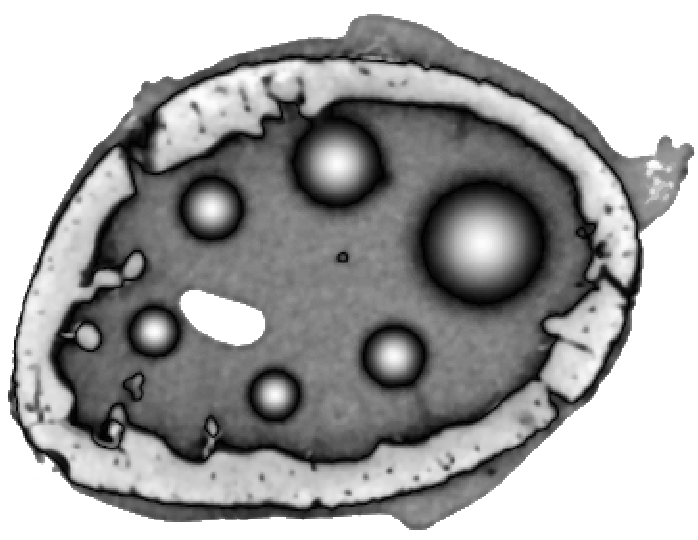

To test the proposed penalty in regularized tomographic reconstruction we designed an analytical phantom which consists of a smooth (two Gaussians and two parabolas) and piecewise-constant (one rectangle) functions (see Fig. 1).

To simulate emission tomography reconstruction we designed a more realistic phantom from the high-quality X-ray scan of a mice bone. The data was acquired on a Nikon Metris Custom Bay cone-beam scanner at the Henry Moseley Manchester X-ray facility, and was reconstructed with the Feldkamp algorithm (see Fig. 7 (left)). We thresholded the obtained reconstruction and added six gaussians with various kernel widths (see Fig. 7 (middle and right)).